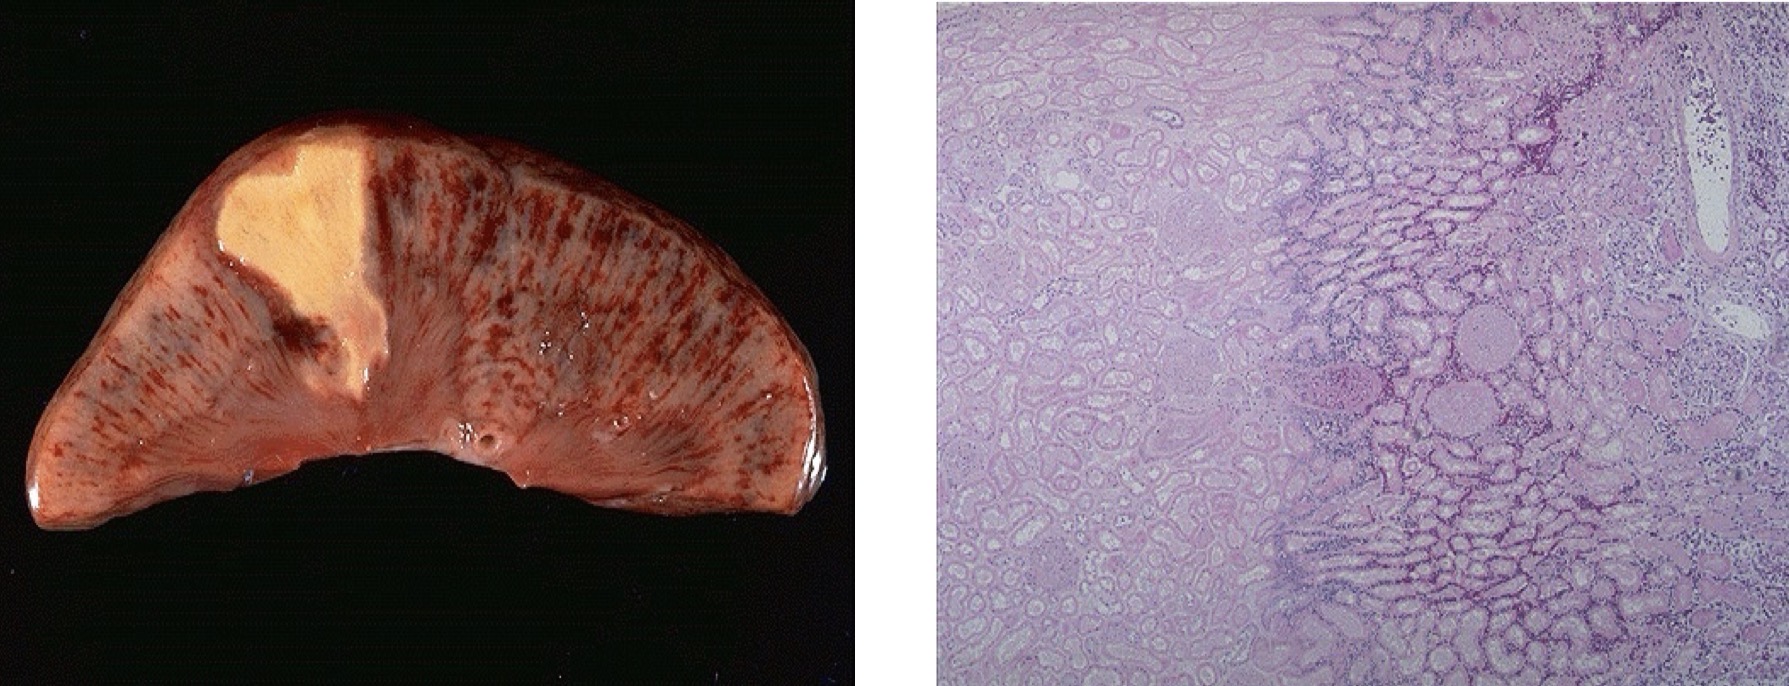

1. Describe the gross morphology in A?

2. Describe the microscopic morphology in B?

3. Identify the condition.

1- It shows nutmeg liver (red central areas surrounded by tan viable parenchyma).

2-It shows centrilobular hepatic necrosis with hemorrhage and scattered inflammatory cells.

3- Liver with chronic passive congestion and hemorrhagic necrosis.